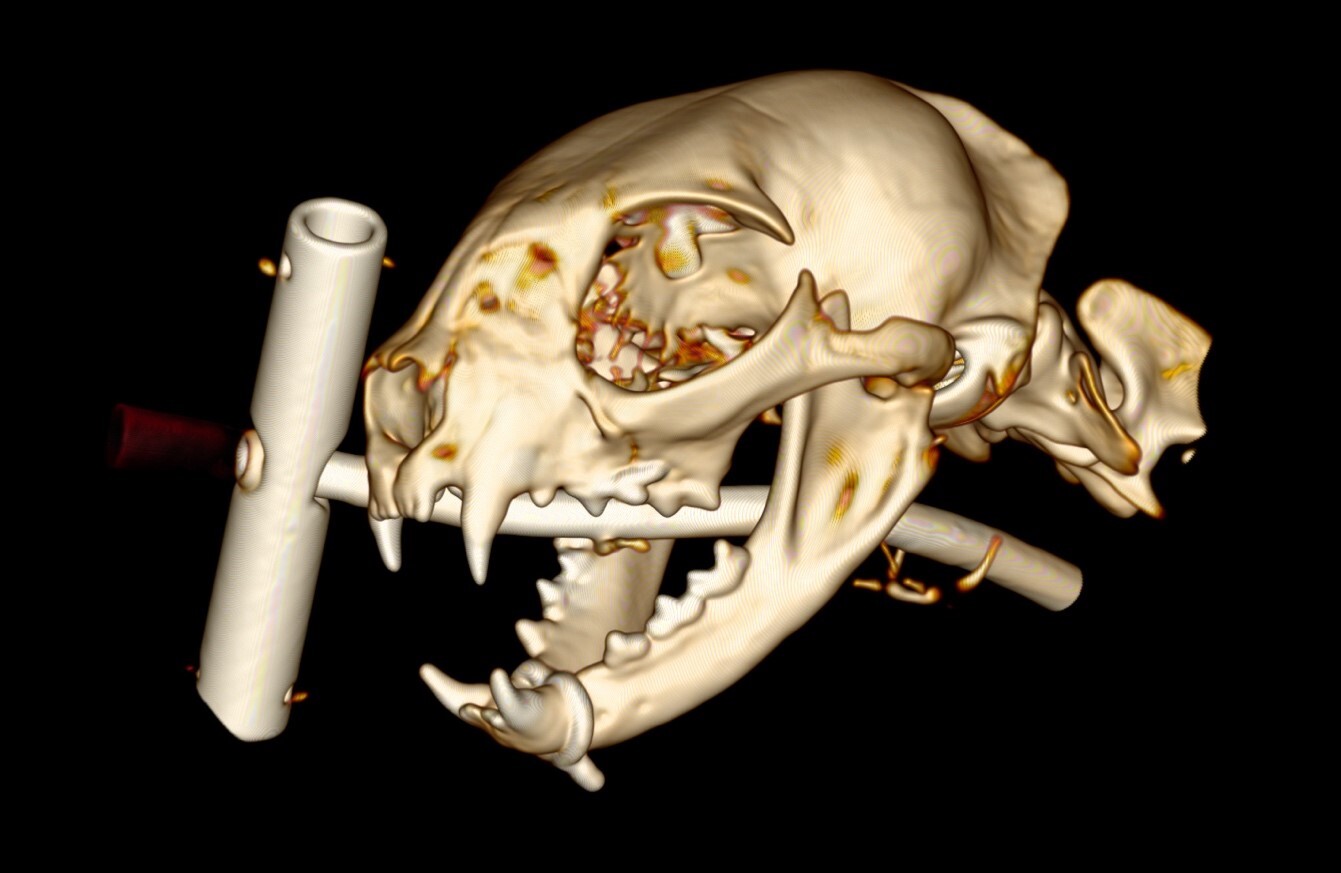

再び全身麻酔をかけ、頭部・口腔内の検査と抜糸を行いました。

手術から約2ヶ月経過した頭部のCT画像(3Dデータ)

損傷部に特に問題はなく、体調共に良好でした。下顎のワイヤーは残したままで経過を見ました。その後は経過をみてワイヤーを除去する予定でしたが、行方不明になってしまったため状態を確認することができなくなってしまいました。